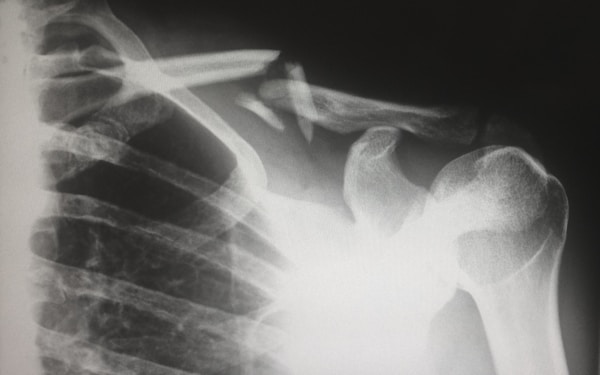

When studying the effects of DNA on injury susceptibility, there are two primary areas of focus: bone structure and muscle composition. Both of these factors can play a major role in determining how likely a person is to experience injury.

Bone structure is determined by our DNA. The genes responsible for bone formation are responsible for the shape, size, and strength of our bones. People with certain genetic mutations can have bones that are weaker than average, making them more prone to fractures, dislocations, and other types of injuries. Similarly, people with certain genetic mutations can have bones that are stronger than average, making them less susceptible to injury. Muscle composition is also influenced by our DNA. The genes responsible for muscle development determine how our muscles are formed and how powerful they are. People with certain genetic mutations can have muscles that are weaker than average, making them more prone to strains and sprains. Learn if you have certain genetic susceptibilities to injuries or diseases with the raw DNA data upload tool offered by GenomeLink.